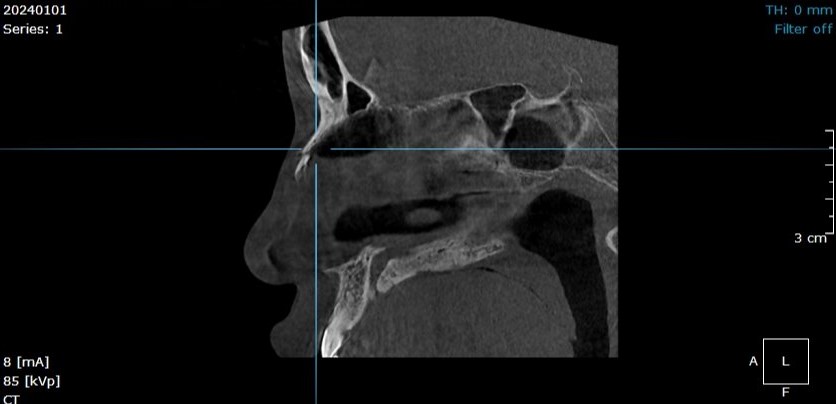

🪻Bệnh nhân bị chấn thương đến thăm khám tại Hồng Hoàng, thông qua hình ảnh chụp CLVT răng hàm mặt dưới đây chẩn đoán bệnh nhân bị gãy xương mũi.

👉 Phát hiện được các tổn thương về xương ở khu vực hàm mặt: gãy xương, rạn xương, u nang...